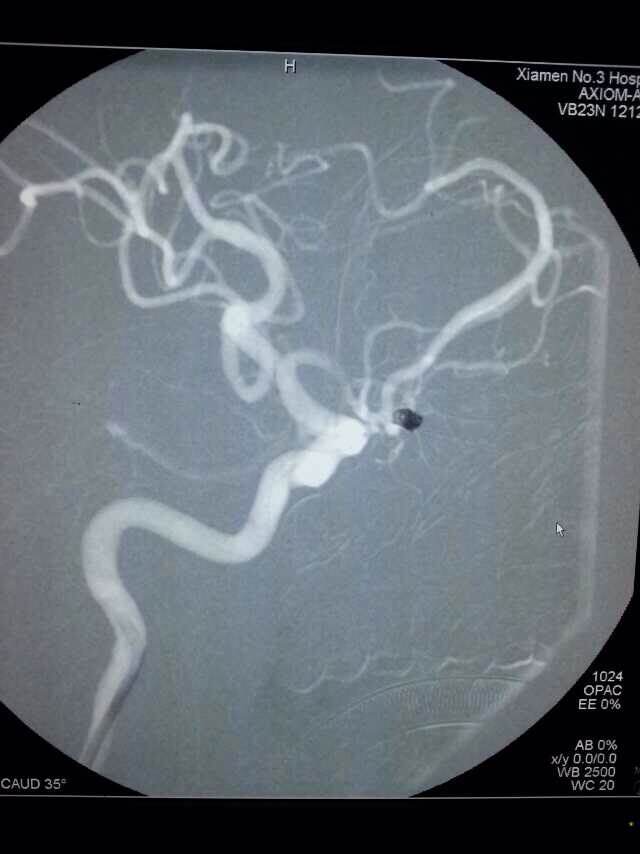

2014520是个特别的日子,第三伦理片 手术室灯火通明,神经外科调集所有的技术团队手术一台接一台,有脑动脉瘤破裂的,有脑外伤出血的,忙碌不停。